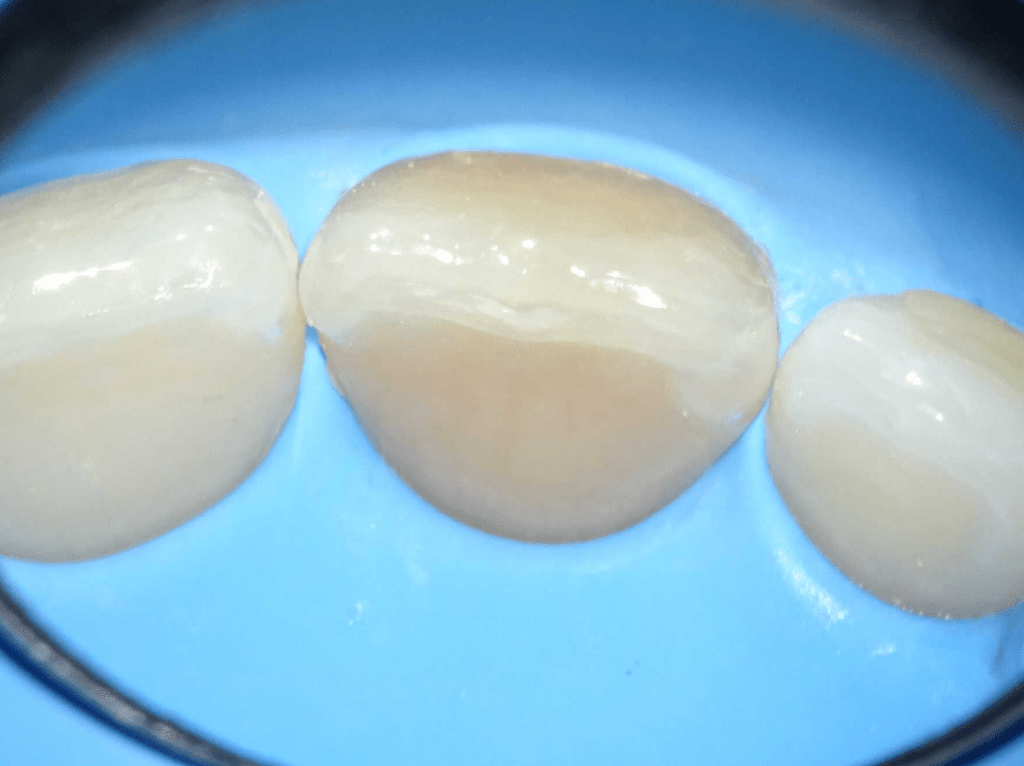

Acceso ultraconservador a través de incrustación reciente